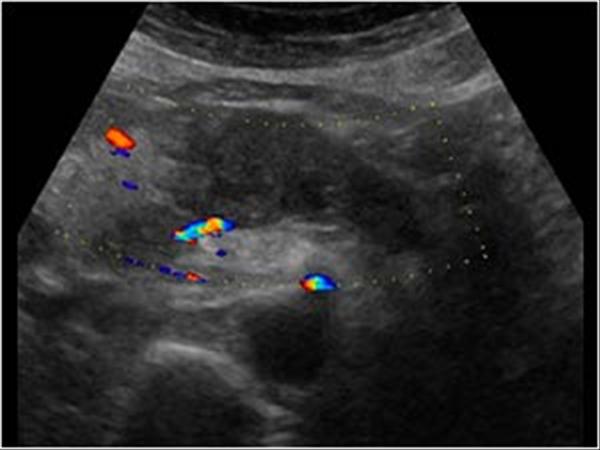

U tụy

» Thông tin: Nữ giới – 57 tuổi.

» Lâm sàng: Sút cân.